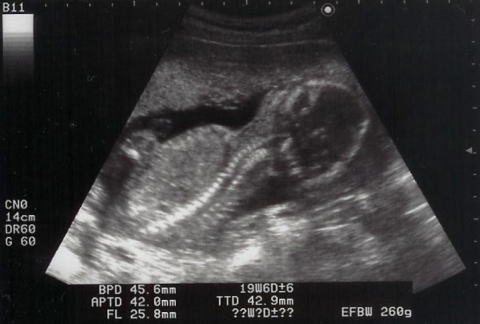

shigeruはとても元気に動いていて、心音を探すのが大変でした。エコーでは手をグーパーしながら、時々ママを見ていました。この写真は苦しそう?早く出てきたいの?でも、あと21週間はママのお腹にいてね。ママは体重が4週で1.6kg増。助産師さん・お医者様に注意されてしまいました。

仰向けでshigeruの形が判ります。